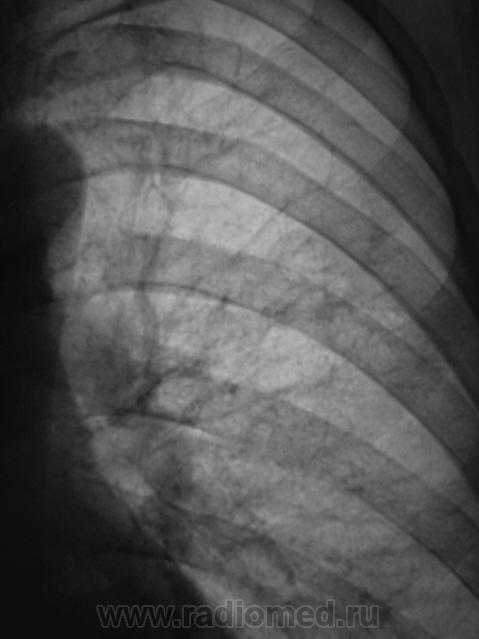

Томограммы.

По мне, так пневмония. Пролечить, посмотреть динамику.

Был нетак давно похожий случай, так же постродал S3,  в связи с локолизацией и консультацией заведующей отправил больного КТД (крайтубдиспансер), там пролечили антибиотиками и отправили домой,  на контроле всё чисто.

Добрый вечер, Валентин Львович. Жалоб нет, или не предъявляет. При туберкулезе - и инфильтрация, и распад, и т.д., а они не предъявляют - тогда ТБС.

По моему S2.

Да ведь у S3 граница по междолевой.